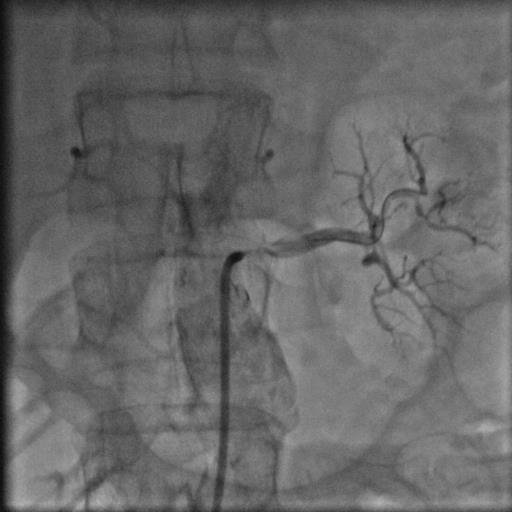

44 yaşında şeker hastalığı olan hastamız dirençli yüksek tansiyon şikayetiyle bize başvurdu. Herhangi bir sebep bulunamayan hastamız 2 yıldan beri cesitli ilaçlar kullanmasına rağmen tansiyonunun düşürülemediğini söylüyordu. Yaptiğımız detaylı muayene ve tetkikler sonucu böbrek damarının tıkalı olduğunu tesbit ettik ve yaptıgımız stent işlemi sonrasında hastamız normal tansiyon değerleriyle taburcu edildi..